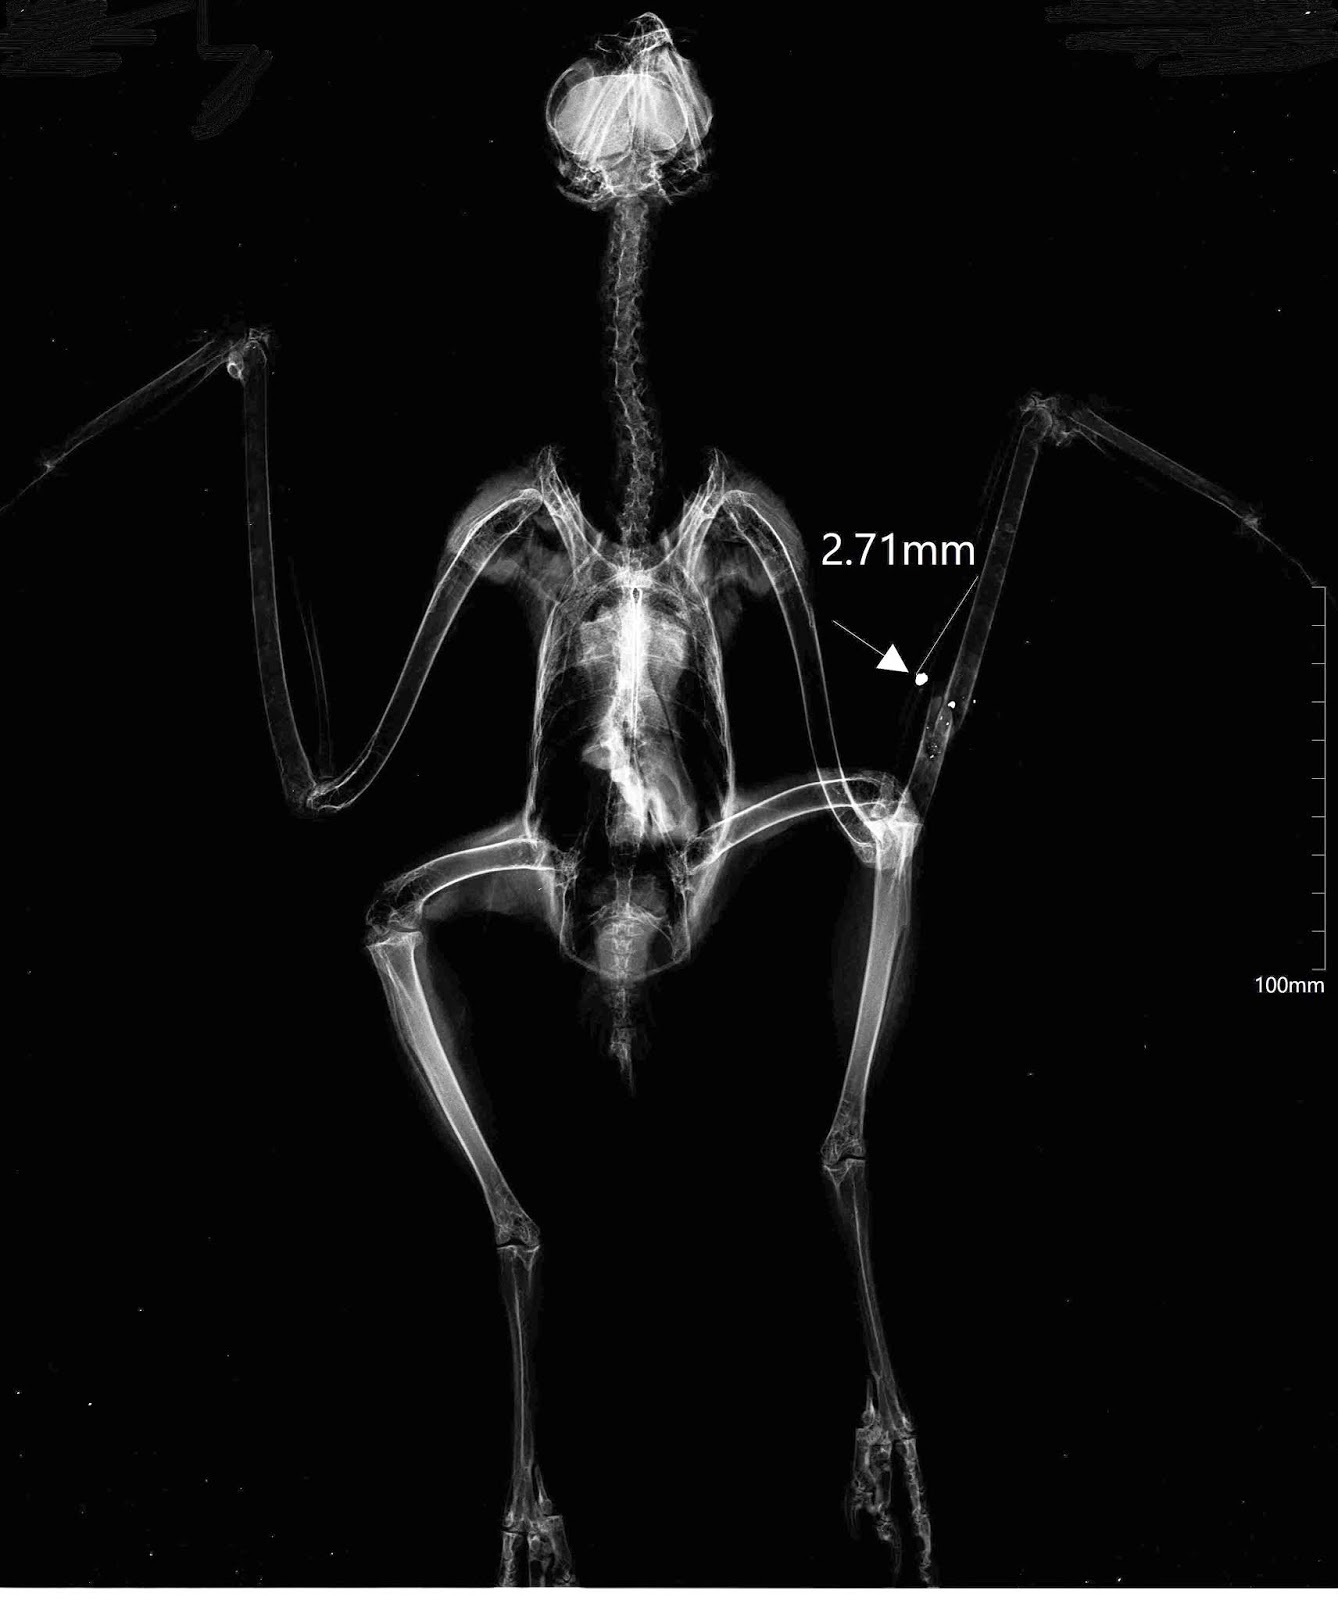

![]() |

| Raio-X da garça-real. |

A terceira ave, uma garça-real (Ardea cinerea), a maior garça que ocorre em Portugal, ingressou dia 8 de Outubro com três chumbos visíveis no corpo, e uma fratura na asa direita, na qual foi colocada uma ligadura.